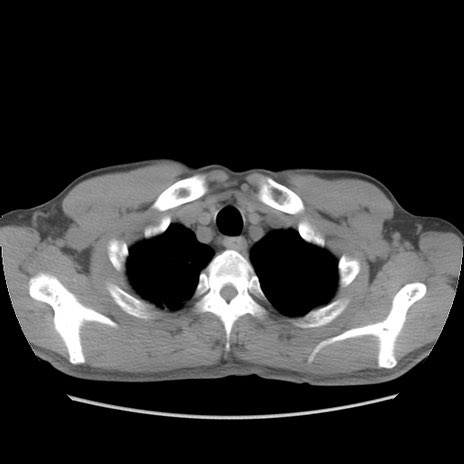

症例56 CT(横断像)

脂肪ウインドウ